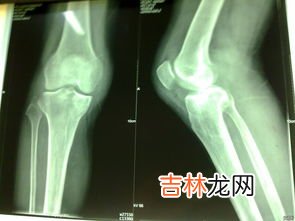

文章插图